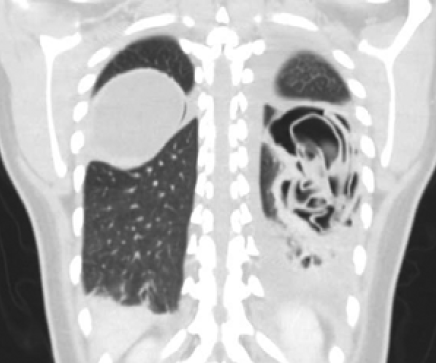

Imágenes y Cirugía

|

Natalia Gutiérrez Corral, Guillermo Carreño Villarreal, María Fernández Hevia, Nuria Aguado Suárez